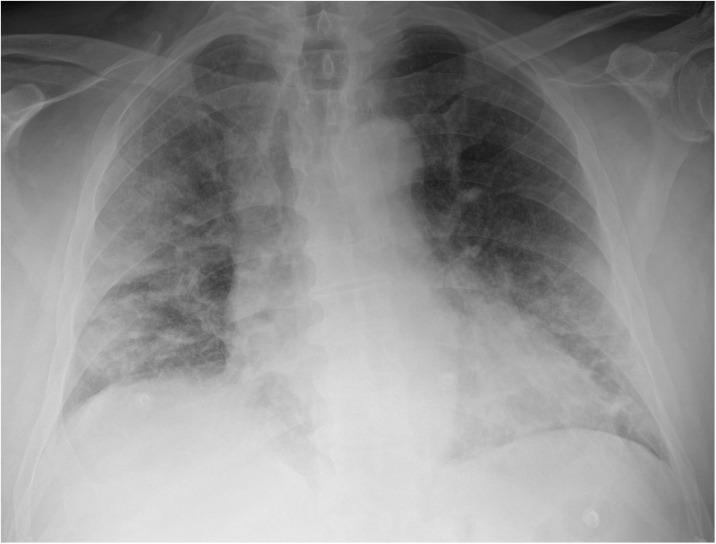

To report real-world diagnostic performance of chest x-ray (CXR) readings during the COVID-19 pandemic.

In this retrospective observational study we enrolled all patients presenting to the emergency department of a Milan-based university hospital from February 24th to April 8th 2020 who underwent nasopharyngeal swab for reverse transcriptase-polymerase chain reaction (RT-PCR) and anteroposterior bedside CXR within 12 h. A composite reference standard combining RT-PCR results with phone-call-based anamnesis was obtained. Radiologists were grouped by CXR reading experience (Group-1, >10 years; Group-2, <10 years), diagnostic performance indexes were calculated for each radiologist and for the two groups.

Group-1 read 435 CXRs (77.0 % disease prevalence): sensitivity was 89.0 %, specificity 66.0 %, accuracy 83.7 %. Group-2 read 100 CXRs (73.0 % prevalence): sensitivity was 89.0 %, specificity 40.7 %, accuracy 76.0 %. During the first half of the outbreak (195 CXRs, 66.7 % disease prevalence), overall sensitivity was 80.8 %, specificity 67.7 %, accuracy 76.4 %, Group-1 sensitivity being similar to Group-2 (80.6 % versus 81.5 %, respectively) but higher specificity (74.0 % versus 46.7 %) and accuracy (78.4 % versus 69.0 %). During the second half (340 CXRs, 81.8 % prevalence), overall sensitivity increased to 92.8 %, specificity dropped to 53.2 %, accuracy increased to 85.6 %, this pattern mirrored in both groups, with decreased specificity (Group-1, 58.0 %; Group-2, 33.3 %) but increased sensitivity (92.7 % and 93.5 %) and accuracy (86.5 % and 81.0 %, respectively).

Real-world CXR diagnostic performance during the COVID-19 pandemic showed overall high sensitivity with higher specificity for more experienced radiologists. The increase in accuracy over time strengthens CXR role as a first line examination in suspected COVID-19 patients.